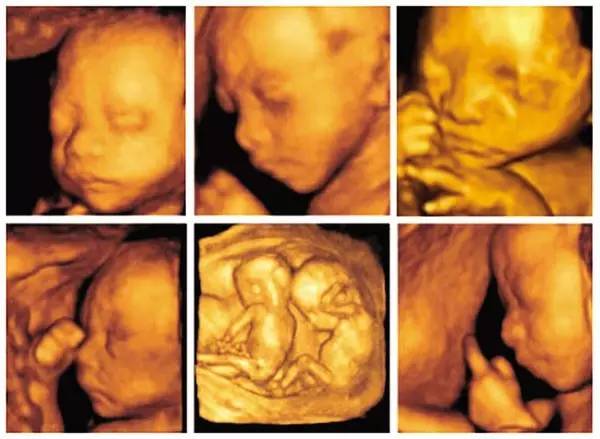

5、三维、四维彩超

3D彩超,指的是平面黑白B超再加上彩色多普勒,形成静态的三维图片,侧重观察五脏六腑是否畸形,排除结构畸形。

四维彩超,就是把不同时间的3D超声图像连成动图,实时的看到宝宝的动态活动,观察内容除了3D彩超内容外,还观察运动神经系统是否正常,运动是否协调。

三维和四维彩超,二选一即可。可以做胎儿大体解剖结构筛查,包括大脑、面部、心脏、腹部、四肢等,以及羊水多少,胎盘厚度,脐带情况。